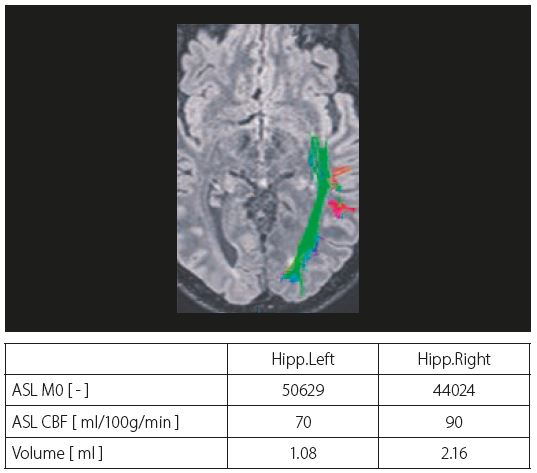

На рисунку 2 показано склероз лівого гіпокампу у пацієнта з лівосторонньою скроневою епілепсією.

Зображення FLAIR показують гіперінтенсивний сигнал у лівому гіпокампі, а MPRAGE використовується для класифікації склерозу. ROI встановлюються як на нормальній зоні, так і на склерозі карт ADC і церебрального кровотоку. ASL показує ліву скроневу гіпоперфузію.

У таблиці на рисунку 3 показано значення церебрального кровотоку як для нормальної зони, так і для склерозу: виявлено зниження на 25% церебрального кровотоку для склерозу, що можна пояснити низькою васкуляризацією цієї області.

Рис. 3. Показано оптичні тракти, накладені на аксіальний MPR FLAIR. У таблиці наведені абсолютні значення церебрального кровотоку (CBF) в нормі та в зоні склерозу.

Пацієнту було рекомендовано операцію та проведено трактографію для візуалізації оптичних волокон. Для нейрохірурга важливо знати точний маршрут цих трактів, щоб запобігти пошкодженню волокон.